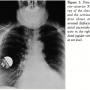

Subsequent posterior-anterior x-ray of the chest  and cervical area showed a displaced atrial pacemaker wire as the cause of the intermittent clinical and electrocardiographic phenomenon (Figure 1). Additionally, duplex-ultrasound of the jugular vein revealed a clinically asymptomatic, non-occlusive, floating thrombus formation at the tip of the displaced lead (Figure 2).